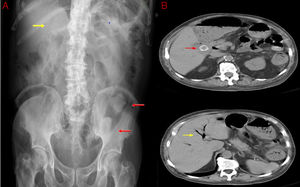

A 78-year-old man exhibited repeated episodes of vomiting, diffuse abdominal pain and constipation for 10 days. One year previously, he had suffered from biliary colic but cholecystectomy was not performed because of high surgical risk. Physical examination showed a mass on the left side of the abdomen and increased bowel sounds. The blood count showed light leukocytosis and normal metabolic profile. An abdominal radiography showed Rigler's triad (Fig. 1, Image A): pneumobilia (yellow arrow), small-bowel dilatation, and two ectopic gallstones in the sigmoid colon (red arrows). Computerized tomography confirmed the presence of intra and extrahepatic pneumobilia (Fig. 1, Image B), as consequence of cholecysto-colonic fistula secondary to cholelitiasis. Gallstone ileus is a rare complication of gallstone disease, and in less than 4% of cases the gallstone is located in the sigmoid colon. The diagnosis is not always straightforward and usually depends on radiographic findings, although the classic Rigler¿s triad is described in fewer than half of patients1-3. A laparotomy was performed and a right hemicolectomy was necessary because of colonic perforation. The patient underwent successful surgery and no post-operative complications ensued.